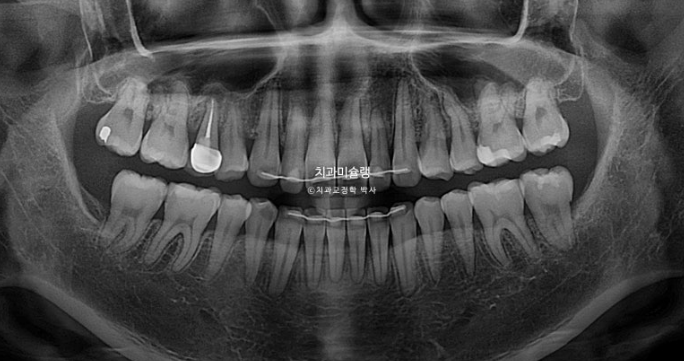

1년 5개월에 걸친 재교정 기간동안 치근흡수도 없습니다.

치근평행도는 좋네요.